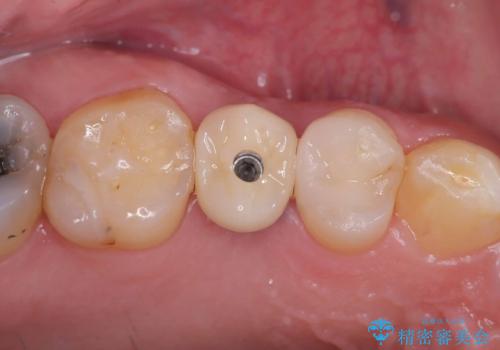

インプラントはインプラント周囲炎になりにくいスクリュータイプを使用しています。

右上4番は虫歯になっていたので、虫歯を除去後、セラッミクインレーで治療を行いました。

オペの回数を最小にする事で患者様の治療への負担が減り、治療期間も従来の治療より大幅に短くする事が可能です。